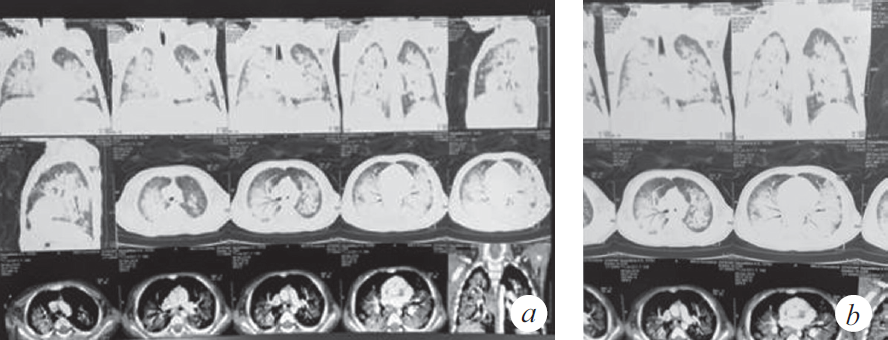

Рис. 6. Компьютерная томография органов грудной клетки (через 5 мес. от дебюта заболевания) (a). КТ-признаки интерстициального поражения легочной ткани с увеличением площади консолидации в медиальных отделах обоих легких с сохранением в базальных отделах S2, S6, S10 справа и S6 слева (b)

Fig. 6. CT of the chest organs (5 months after the onset of the disease) (a). CT signs of interstitial damage to the lung tissue with an increase in the area of consolidation in the medial sections of both lungs, while maintaining in the basal sections S2, S6, S10 on the right and S6 on the left (b)